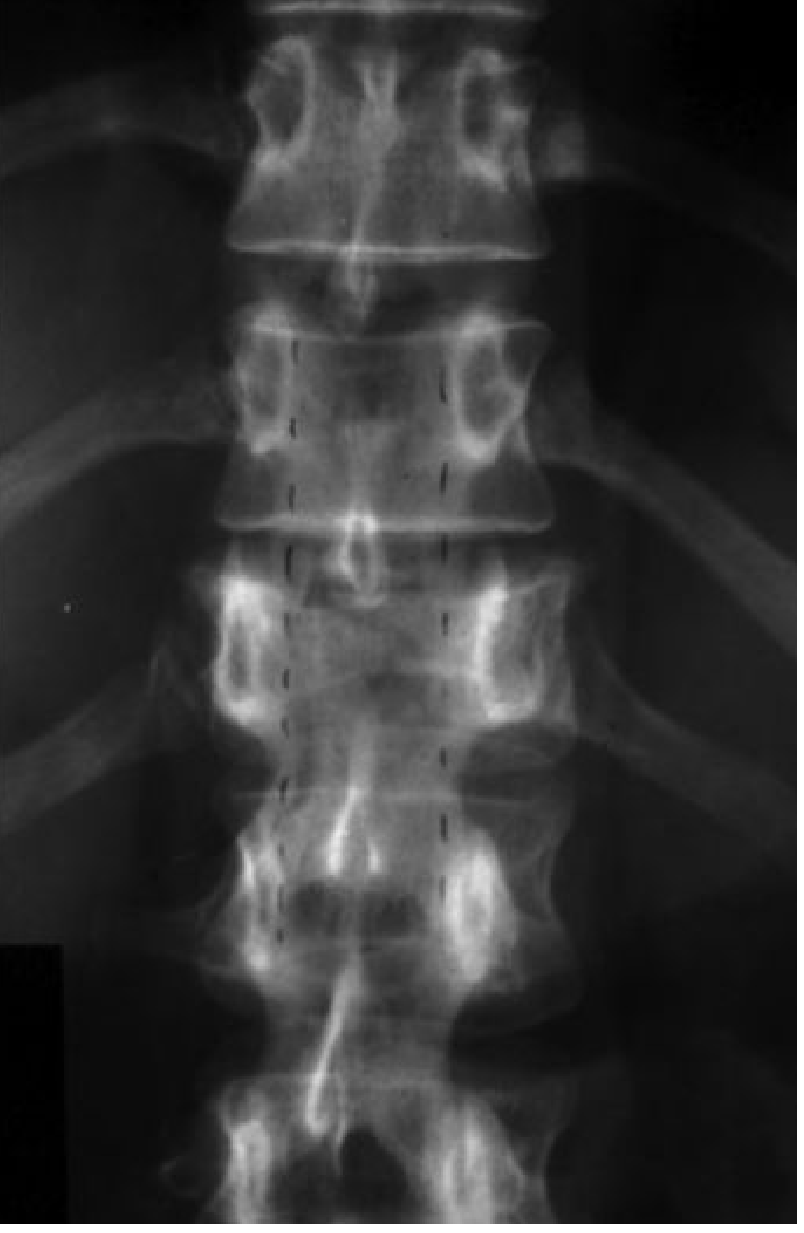

Below is an x-ray of lumber spine of 35 year old man , both Ap and Lat view is attached as well.

Lumbar Spine X-Ray Analysis — 35-Year-Old Male

AP View Findings

Alignment:

• The lumbar vertebral column appears midline with no obvious lateral curvature (no scoliosis detected on this view).

• Vertebral bodies are normally aligned in the coronal plane.

Vertebral Bodies:

• Vertebral body heights appear relatively preserved across L1–L5.

• No obvious compression fractures or wedging.

Disc Spaces:

• There is mild disc space narrowing visible, most apparent in the lower lumbar levels (L4–L5, L5–S1).

Pedicles & Posterior Elements:

• Pedicles are visible and appear intact bilaterally.

• No obvious lysis of pedicles (no "winking owl" sign to suggest metastatic disease).

Sacroiliac Joints:

• Both SI joints appear symmetrical and unremarkable — no obvious sacroiliitis or erosions.

Soft Tissues:

• Psoas shadow appears present bilaterally.

• Bowel gas pattern visible — no gross soft tissue mass.

This 35-year-old male has plain radiographic evidence of lumbar spondylosis with disc space narrowing at L4–L5 and L5–S1, loss of lumbar lordosis, and early endplate changes. These findings are premature for his age. An MRI would be the definitive next step to evaluate for disc herniation, neural foraminal stenosis, or canal compromise, particularly if he is symptomatic with low back pain ± radiculopathy.